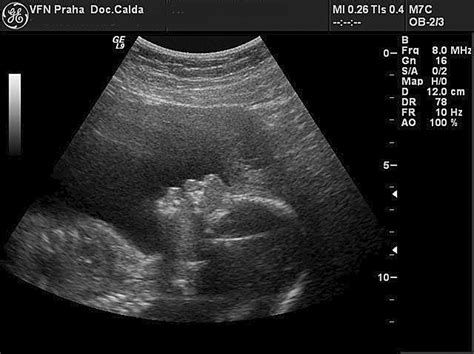

Morfologický ultrazvuk, často označovaný ako "veľký ultrazvuk", predstavuje kľúčový moment v tehotenstve. Toto podrobné vyšetrenie, ktoré sa zvyčajne vykonáva medzi 18. a 22. týždňom tehotenstva, je zamerané na dôkladné posúdenie anatómie plodu a jeho rastu. Jeho cieľom je včas odhaliť prípadné vrodené vývojové chyby alebo anomálie, ktoré by mohli ovplyvniť zdravie dieťaťa. V súvislosti s týmto vyšetrením sa však u budúcich rodičov často objavujú otázky týkajúce sa jeho rozsahu, dĺžky trvania a najmä nákladov, čo môže viesť k miernemu zmäteniu, ako naznačuje aj skúsenosť s cenou za vyšetrenie u konkrétneho lekára.

Morfologický ultrazvuk je oveľa komplexnejší ako bežné ultrazvukové vyšetrenia vykonávané v skorších fázach tehotenstva. Lekár počas neho detailne skúma všetky orgány a systémy plodu, aby sa uistil o ich správnom vývoji. Medzi hlavné oblasti záujmu patria:

Toto vyšetrenie poskytuje nielen dôležité informácie o zdraví dieťaťa, ale aj emocionálny zážitok pre rodičov, ktorí prvýkrát vidia svoje dieťa v takomto detailnom zobrazení.

Moderná ultrazvuková technológia neustále napreduje, čo umožňuje lekárom vykonávať čoraz presnejšie a detailnejšie vyšetrenia. Najnovšie prístroje poskytujú vynikajúcu kvalitu obrazu, často v 3D a dokonca aj 4D zobrazení, ktoré umožňujú rodičom vidieť svoje dieťa v reálnom čase. Tieto technologické vymoženosti síce zvyšujú cenu vyšetrenia, ale zároveň poskytujú neoceniteľné diagnostické informácie a silný emocionálny zážitok.

Pri morfologickom ultrazvuku sa lekári zvyčajne spoliehajú na vysoko kvalitné 2D zobrazenie, ktoré je kľúčové pre presné merania a posúdenie anatómie. 3D a 4D zobrazenia sú často doplnkovou službou, ktorá slúži skôr na vizuálne spoznanie dieťaťa.